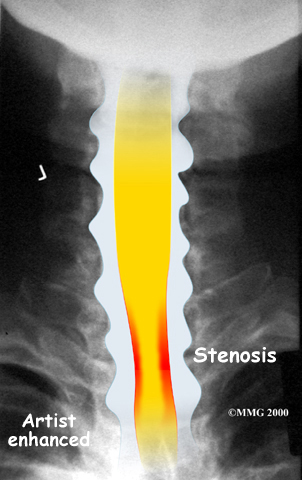

The bony spinal canal normally has more than enough room for the spinal cord. Typically, the canal is just less than ¾ of an inch, or 17-18 millimeters around, which is less than the size of a small bottle cap. Spinal stenosis occurs when the canal narrows to around half an inch, or 13 millimeters or less. When the size drops even further, severe symptoms of myelopathy occur. The symptoms of myelopathy result from the actual pressure against the spinal cord itself as well as the reduced blood supply in the spinal cord as a result of the pressure.

Degeneration is the most common cause of spinal stenosis. Wear and tear on the spine from normal aging and from repeated stress and strain can cause many problems in the cervical spine. The intervertebral disc can begin to collapse, shrinking the space between the vertebrae. Bone spurs (small bony projections) may form that protrude into the spinal canal and reduce the space available for the spinal cord. The ligaments that hold the vertebrae together may become thicker and can also push into the spinal canal. All of these conditions narrow the spinal canal.

X-rays are used to look for the cause of pressure against the spinal cord. X-ray images can show if degeneration has caused the space between the vertebrae to collapse and may show if a bone spur is pressing against the spinal cord.

If more information is needed, a magnetic resonance imaging (MRI) scan may be ordered. The MRI machine uses magnetic waves rather than X-rays to show the soft tissues of the body. This test gives a clear picture of the spinal cord and can show where it is being squeezed. An MRI machine creates pictures that look like slices of the area your healthcare professional is interested in. This test does not require any special dye or a needle.

A computed tomography (CT) scan may also be ordered. The CT scan is a detailed X-ray that lets doctors see slices of bone tissue. The image can show if bone spurs are protruding into the spinal column and taking up space around the spinal cord.